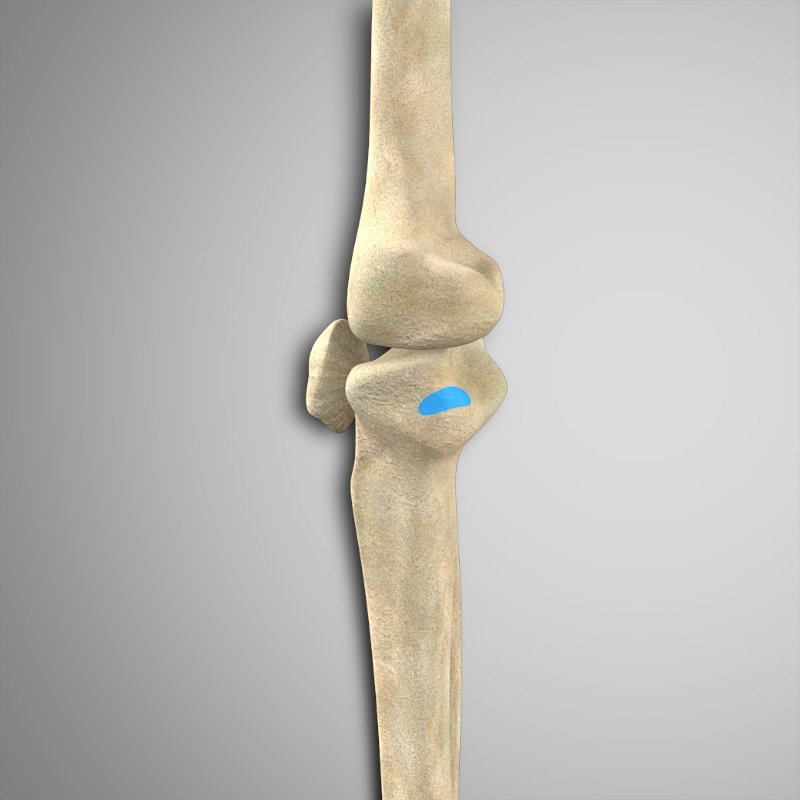

- Bíceps femoral (ambas cabezas) – Cabeza del peroné

- Semimembranoso – Cóndilo tibial medial posterior

- Semitendinoso – Tendón anserino.